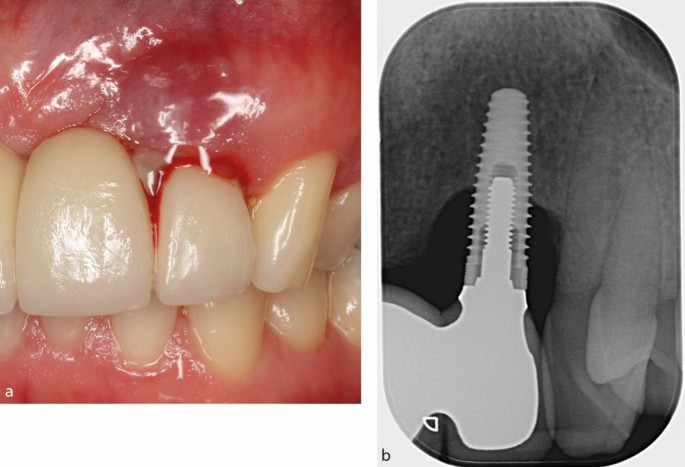

# 4. 후기 실패(Late Failure)의 병태생리 — Peri-implantitis

Peri-implantitis는

임플란트 주위의 염증 + 골 파괴가 동반된 상태.

4-1. 주요 병태생리

✔ 1) Dysbiosis(미생물 불균형)

- Porphyromonas gingivalis

- Tannerella forsythia

- Treponema denticola

→ 치주염과 매우 유사한 패턴

✔ 2) Titanium wear particles

2024 Biomaterials 연구:

Ti wear가 매크로파지 반응을 활성화 →

IL-6·TNF-α 증가 → 골 파괴 가속

✔ 3) Biofilm 형성

임플란트 표면의 거칠기·마이크로구조 영향

✔ 4) 기계적 스트레스

Implant–bone interface의 재흡수